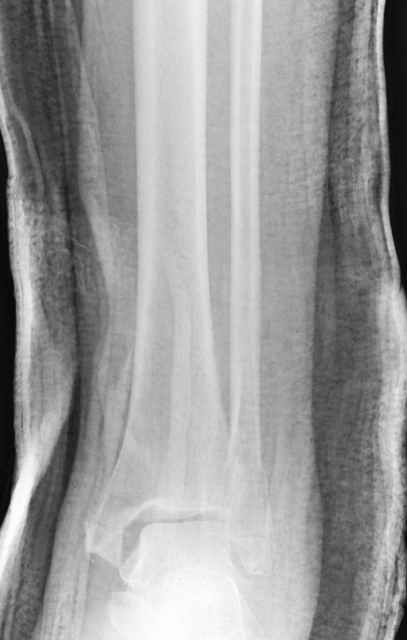

Pilon fracture:

-С появлением новых имплантов, которые делятся на правые и левые, задней или латеральной аппликации, жесткие с локинг концепт, которые сидят на кости анатомически, применение 1/3 тубулярных пластинок

отходит на второй план из-за ее слабости. Если применить 2 пластины уложенные друг на друга, слабость этих пластинок можно скомпенсировать.

Слабая несостоятельная пластина приводит к вальгусной деформации и риск осложнений нарастает, особенно если линия перелома находится выше

метафизарной зоны, в диафизе, где имеется риск замедленного сращения, тогда адекватно применение более жесткой конструкции 3.5 мм динамической компрессионной пластины.

При косых переломах малоберцовой кости применение пластин отличается от обычных, показание antiglade technique-методика против скольжения, потому что укорочение длины малоберцовой кости чреваты ранними артрозами.

Из работ Ramsey and Hamilton, Yablon et., укорочения на 1мм

малоберцовой кости, уменьшает на 42% контактную поверхность между

малоберцевой и таранной кости, которое в свою очередь приводит к

увеличению давления на остальные части суставной поверхности, что

является предпосылкой раннего артроза.